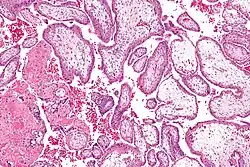

Chorionvilli en decidua

Chorionvilli (H&E-kleuring)